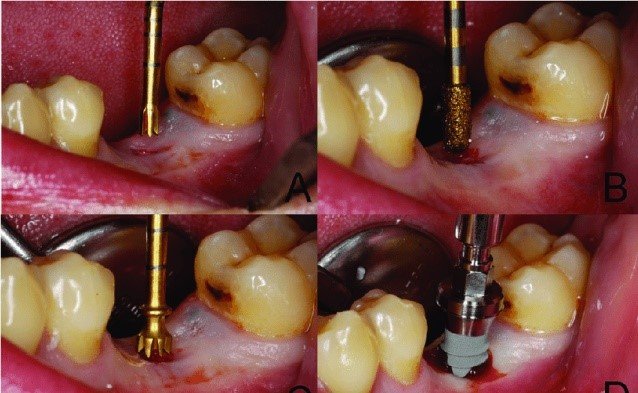

Sequential Drilling Protocol Excellence:

Contemporary techniques of zygomatic implants employ systematic drilling sequences that prioritize safety and accuracy. Entry point establishment based on prosthetic requirements, progressive drilling with specialized instrumentation, trajectory verification using multiple anatomical landmarks, and implant selection based on intraoperative measurements ensure optimal placement.

Manual insertion techniques achieving controlled torque values of 35-45 Ncm prove optimal for primary stability while avoiding excessive stress on bone structures. The recent Eazygoma approach demonstrates superior outcomes with consistent achievement of >50 Newton insertion torque, enabling reliable immediate loading protocols.